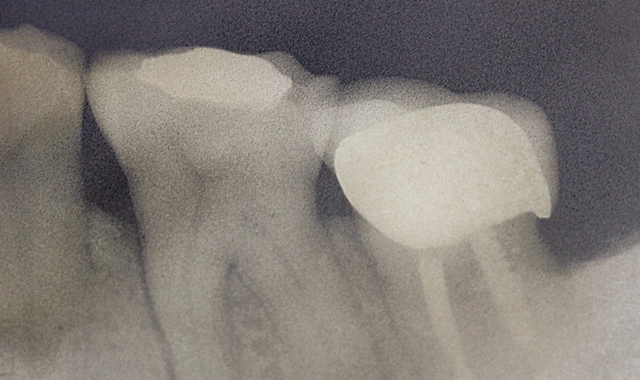

Fig. 1 X-ray of tooth demonstrating lesion around mesial root.

A 51-year-old female patient had her lower first left molar extracted due to a vertical fracture of a root (Fig. 1).